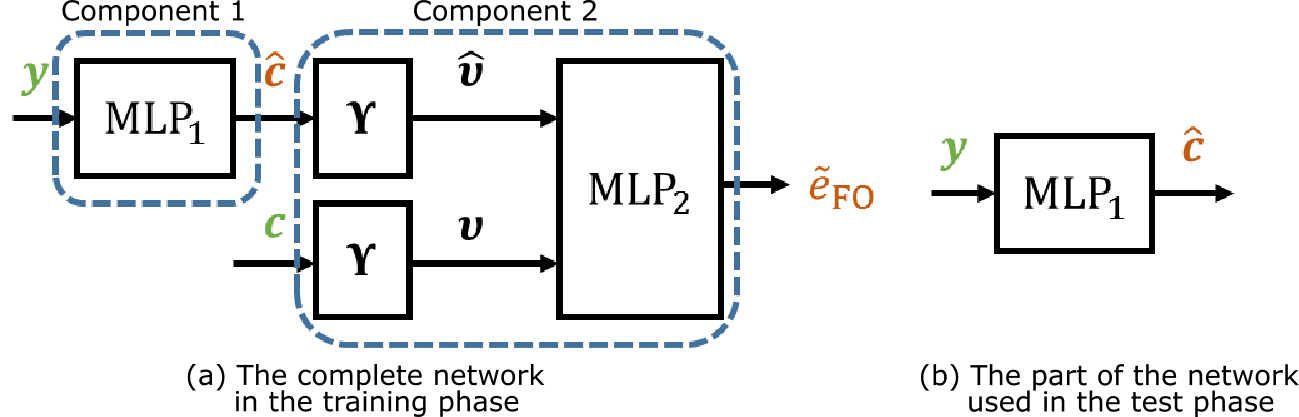

In this work, we propose a deep network structure described in Fig. 2(a), which uses the error of FOs as an auxiliary variable to regularize the computation of the EAP in the training phase. The network comprises two major components: 1) an MLP () that transforms the normalized diffusion signals to the basis coefficients that represent the EAP; and 2) the mapping to compute ODF values in sampled directions for the estimated EAP and the training EAP , followed by another MLP () that approximates the errors of FO estimation using the estimated ODF and the ODF computed from the training EAP. The approximated FO error is denoted by . Note that is known when the sampled directions are determined and is not trainable; and here we use 100 sampled directions. The second MLP is used to approximate the FO error because direct computation of the FO error from the ODF consists of complicated steps and the gradient of the error is difficult to compute during the training process. In this way, the gradient of the FO error can be easily computed for training the network. Like in [4], each MLP has three hidden layers. In each hidden layer, we use 500 units, which are more than the number used in [4], because we observed that EAP computation requires higher expressive power of the MLP. In the test phase, only the first component of the network is needed for EAP computation, as shown in Fig. 2(b).

2.3 Training and Evaluation

The two MLPs were trained separately in three steps as follows. First, we trained the first component () individually using only the mean squared errors of the EAP coefficients as the loss function. This step gives initial estimates of the EAPs and ODFs of the training samples, which are computed from the training diffusion signals. Second, using the estimated ODFs in the first step, the ODFs directly computed from the training EAPs, and the FO errors between these ODFs (computed using their peaks and the error measure in [12]), we trained the second MLP to approximate the FO error computation, where the mean squared errors of FO errors were used as the loss function. Finally, we fixed the second MLP and trained the entire network by minimizing the weighted sum of the approximated FO errors and mean squared errors of EAP coefficients

where is the index of training samples and is a weighting constant (set to empirically). In each training step, we used the Adam algorithm [6] as the optimizer, where the learning rate was 0.001 and the batch size was 128, and 10% of the training samples were used as a validation set to prevent overfitting. The number of epochs was 10 for the first and final training steps and 40 for the second step. The network was implemented using Keras (http://keras.io/).